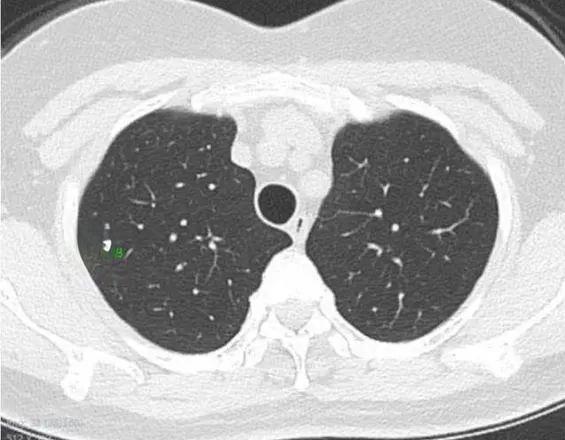

肺结节是指肺内直径小于或等于3厘米的类圆形或不规则形病灶。近年来,随着低剂量螺旋CT筛查的普及,越来越多的肺结节被发现。然而,如何准确判断这些结节的良恶性,成为了困扰患者和医生的一大难题。

在肺部CT检查中,有几个关键指标可以帮助医生初步判断肺结节的性质:

首先是结节的大小。根据中国肺部结节分类、诊断与治疗指南(2016年版),直径≥15毫米的实性结节被视为肺癌高危结节。对于直径介于8毫米至15毫米之间的结节,如果表现出分叶、毛刺、胸膜牵拉等恶性CT征象,也被归类为高危结节。

其次是结节的形状和边缘。恶性结节常呈现出不规则的形状,边缘可能有毛刺或分叶状。相比之下,良性结节的边缘通常较为光滑。

密度是另一个重要指标。肺结节可分为实性结节、部分实性结节和磨玻璃密度结节。其中,部分实性结节的恶性概率最高,其次是磨玻璃密度结节,实性结节的恶性概率相对较低。